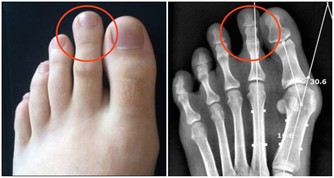

● 道醫通過內觀內證發現:人的筋之根就在腳部,治病要治根,養生也要調根。因此只拉身體的筋,而不把腳部的筋拉開,是治標不治本!